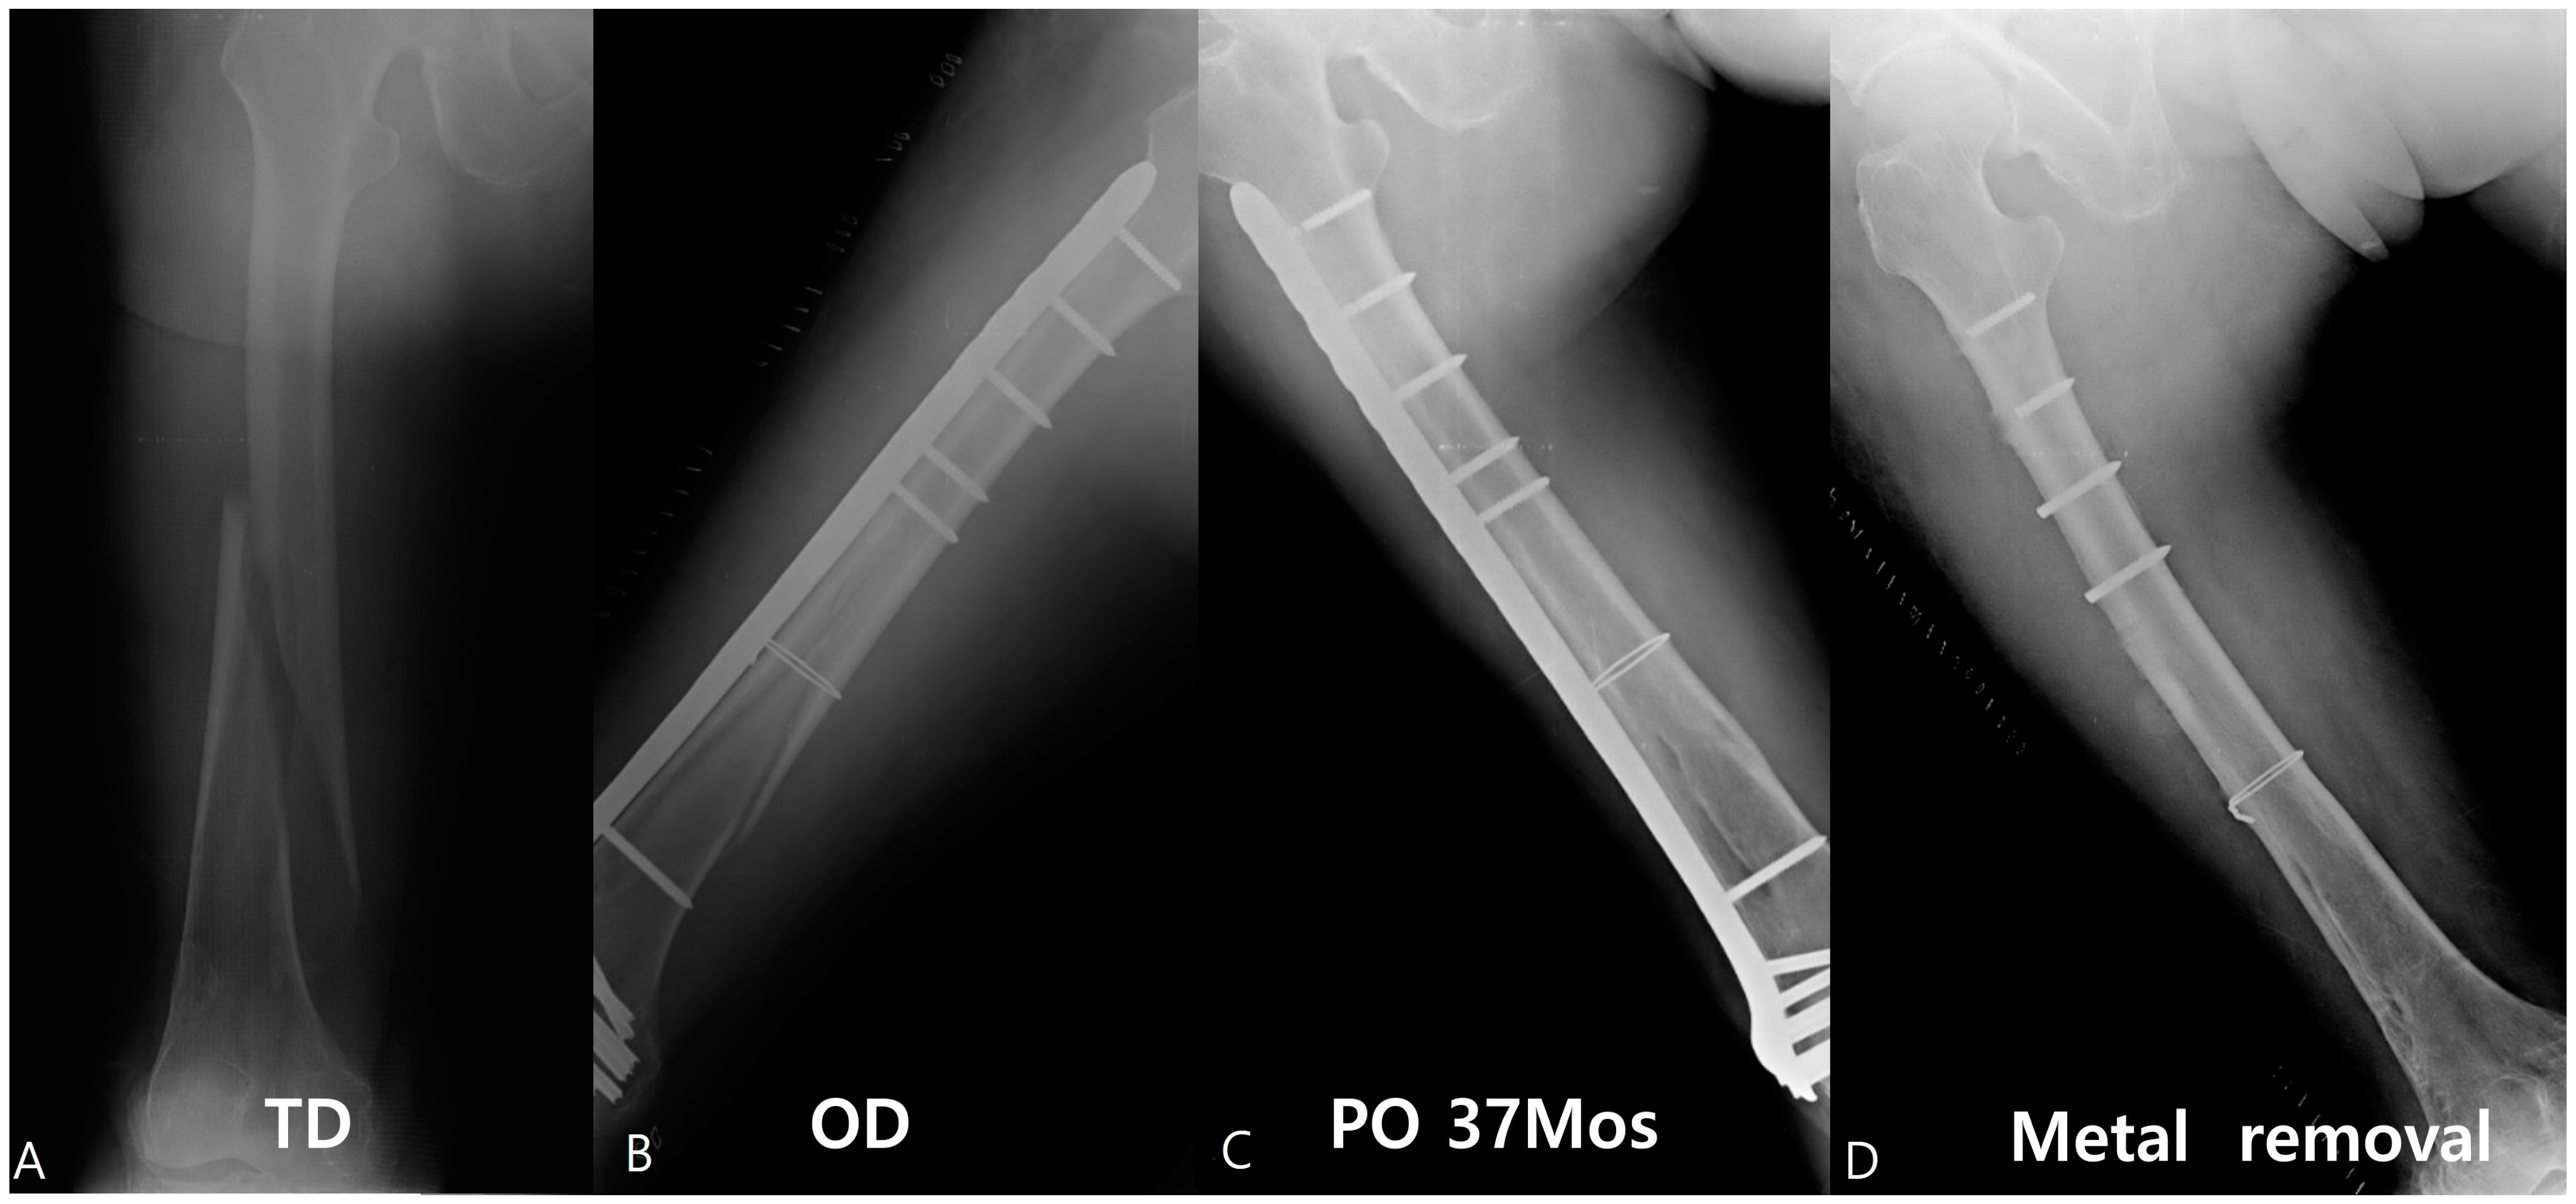

An 83-year-old female patient showed multiple screw breakages at the junction of the screw head and neck after the removal of the plate (Figure 2). An 81-year-old male patient who was reduced by LCP for periprosthetic fractures remained with two broken screws after the removal of the plate (Figure 3).

Figure 2.

An approximately 83-year-old female patient was reduced by the Zimmer® Periarticular Locking Plate (ZPLP®). The fracture pattern was a long spiral with low energy (A). A total of 18 holes, one plate, and one wire were used for reduction (B). This patient was followed up until 37 months (C), and the plate was removed, which showed four broken screws (D).